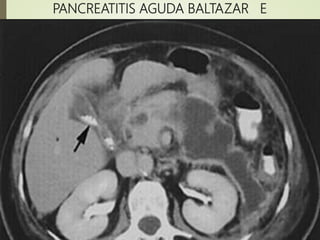

PAG E 4 D+ dos

50% 6

PANCREATITIS AGUDA BALTAZAR E

TÉCNICAS DE IMAGEN oRadiografia simples(Descarta afecciones quirúrgicas abdominales) o Ecografia Abdominal(Para identificación de litiasis biliar) oTomógrafo Computadorizado(TC) o Criterios radiológico de gravedad de Balthazar El sistema desarrollado por Balthazar valora La extensión de la necrosis pancreática y presencia de lesiones extrapancreáticas en niveles de puntuación de 0-10, en que la puntuación 7-10 se asocia com mayor mortalidad 17% y morbilidad 92%

Panc. Grado PtsDescripción morfológica Necrosis Pts PAL A O Páncreas normal O% O PAL B 1 Aumento focal o difuso de páncreas O% O ?? C 2 B+ Inflamación Peri- Pancreática <33% 2 PAG D 3 C+ Colección líquida única 33-50% 4 PAG E 4 D+ dos colecciones líquidas y gás 50% 6